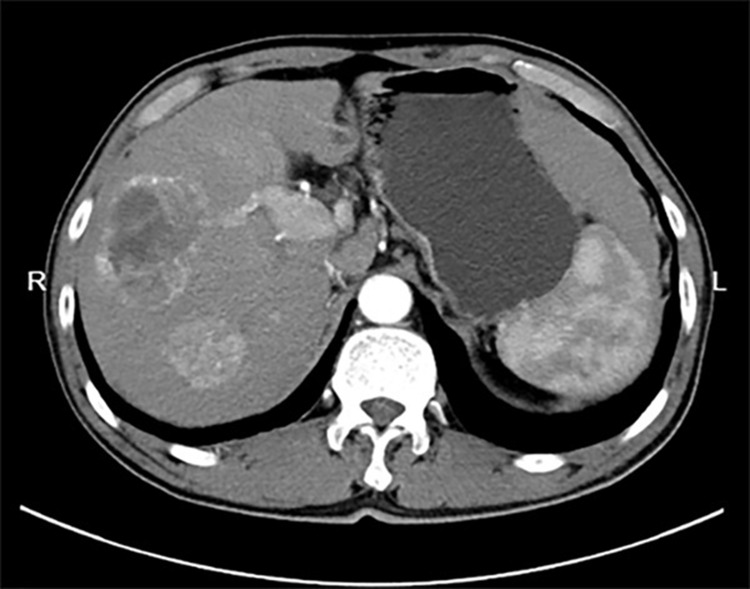

Case presentation: A 63-year-old male with a long-standing history of hepatitis B-related liver cirrhosis and a recent diagnosis of hepatocellular carcinoma presented with a rapidly enlarging painful right-sided thyroid mass associated with swelling but no systemic symptoms such as fever or dysphonia. This prompted a thorough diagnostic workup. Enhanced neck scans indicated a mass potentially originating from the thyroid with tracheal compression, yet crucially, there was no evidence of lung involvement based on the chest CT. Despite the rarity of liver-to-thyroid metastasis, the patient's multifaceted medical history warranted a broad differential diagnosis.

Intervention and outcome: Surgical intervention included a right-sided thyroidectomy and partial left thyroidectomy under general anesthesia. Histopathological examination unexpectedly confirmed the presence of metastatic thyroid cancer originating from the primary liver tumor. This led to further extensive surgical management, including lymph node dissection in the central neck area. The postoperative regimen was adapted to include thyroid hormone replacement and ongoing treatment for hepatocellular carcinoma. The patient's postoperative recovery was closely monitored, reflecting stable disease with no immediate complications.